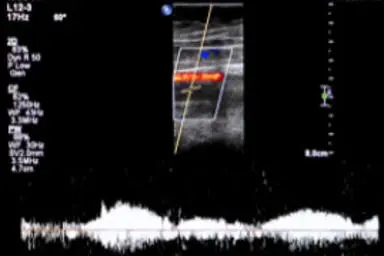

Clinical Tests Prove How Well Revitive Works

After only 10 minutes of using the Revitive Circulation Booster, all symptoms were significantly improved.